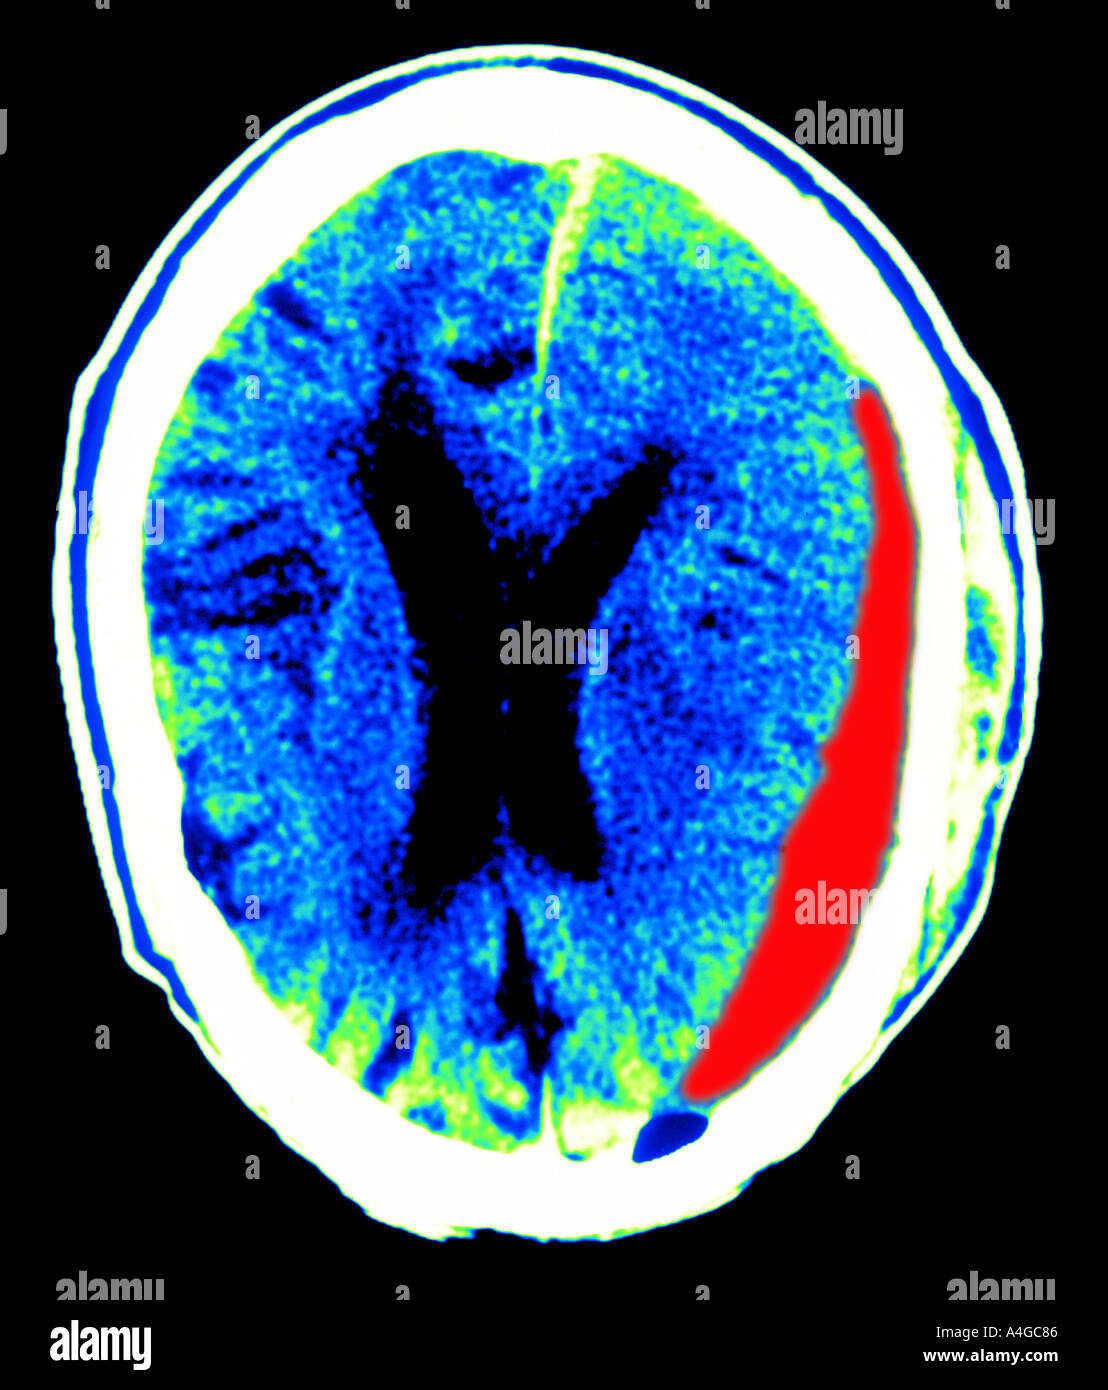

Ematoma subdurale. FPnotebookcom is a rapid access, pointofcare medical reference for primary care and emergency clinicians Started in 1995, this collection now contains 61 interlinked topic pages divided into a tree of 31 specialty books and 737 chapters. Negli anziani invece l’ematoma subdurale può essere causato da un’atrofia cerebrale, la quale a sua volta rende molto fragili le pareti delle vene all’interno del cervello Tra le cause che possono causare l’ematoma subdurale vi sono infine alcuni fattori di rischio, come ad esempio l’uso di farmaci anticoagulanti , il verificarsi di. A subdural hematoma is a type of bleeding in which a collection of blood—usually associated with a traumatic brain injury—gathers between the inner layer of the dura mater and the arachnoid mater of the meninges surrounding the brain It usually results from tears in bridging veins that cross the subdural space Subdural hematomas may cause an increase in the pressure inside the skull, which in turn can cause compression of and damage to delicate brain tissue Acute subdural hematomas.

Ematoma subdurale (SDH) è una emorragia che si verifica sotto la membrana che ricopre il cervello e la colonna vertebrale (dura) E 'spesso causata da trauma cranico, ma può verificarsi senza causa evidente. Emorragia all'interno dello spazio subdurale, Emorragia, subdurale, Emorragia dello spazio subdurale, Emorragia subdurale, Sanguinamento subdurale, Ematoma subdurale Japanese 硬膜下出血, コウマクカシュッケツ, コウマクカケッシュ, 血腫硬膜下, 硬膜下血腫 Swedish Subduralblödning Czech. L'ematoma subdurale si forma principalmente a causa di una rottura delle vene intracraniche risultante da una lesione cerebrale traumatica che passa nello spazio subdurale Molto meno spesso, si verifica a causa di patologia cerebrale vascolare (malformazioni arterovenose e aneurismi cerebrali, ipertensione, vasculite sistemica) e disturbi della coagulazione del sangue (coagulopatia, terapia anticoagulante).

Un ematoma subdurale in genere è causato da eventi di natura traumatica, quali possono essere ad esempio cadute o incidenti che interessino l’area cranica, e in questo caso si parla di ematomi acuti. A subdural hematoma occurs when a blood vessel near the surface of the brain bursts Blood builds up between the brain and the brain's tough outer lining The condition is also called a subdural hemorrhage In a subdural hematoma, blood collects imme. Definition An acute subdural hematoma (SDH) is a clot of blood that develops between the surface of the brain and the dura mater, the brain’s tough outer covering, usually due to stretching and tearing of veins on the brain’s surface.